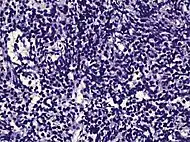

| Small-cell carcinoma | 0.3–2%[14][15][notes 1] | ![]() |

Half of cases have usual acinar components[1] |

||||